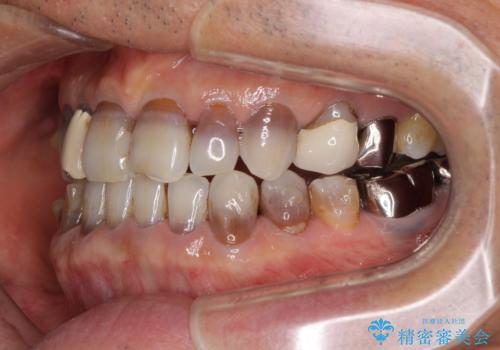

- 前歯のクロスバイトを気にして来院された患者様です。

骨格的に下顎が前方位ではありますが、歯並びが改善されれば正常咬合となることが分かったため、インビザラインを用いて咬み合わせを改善していくこととしました。